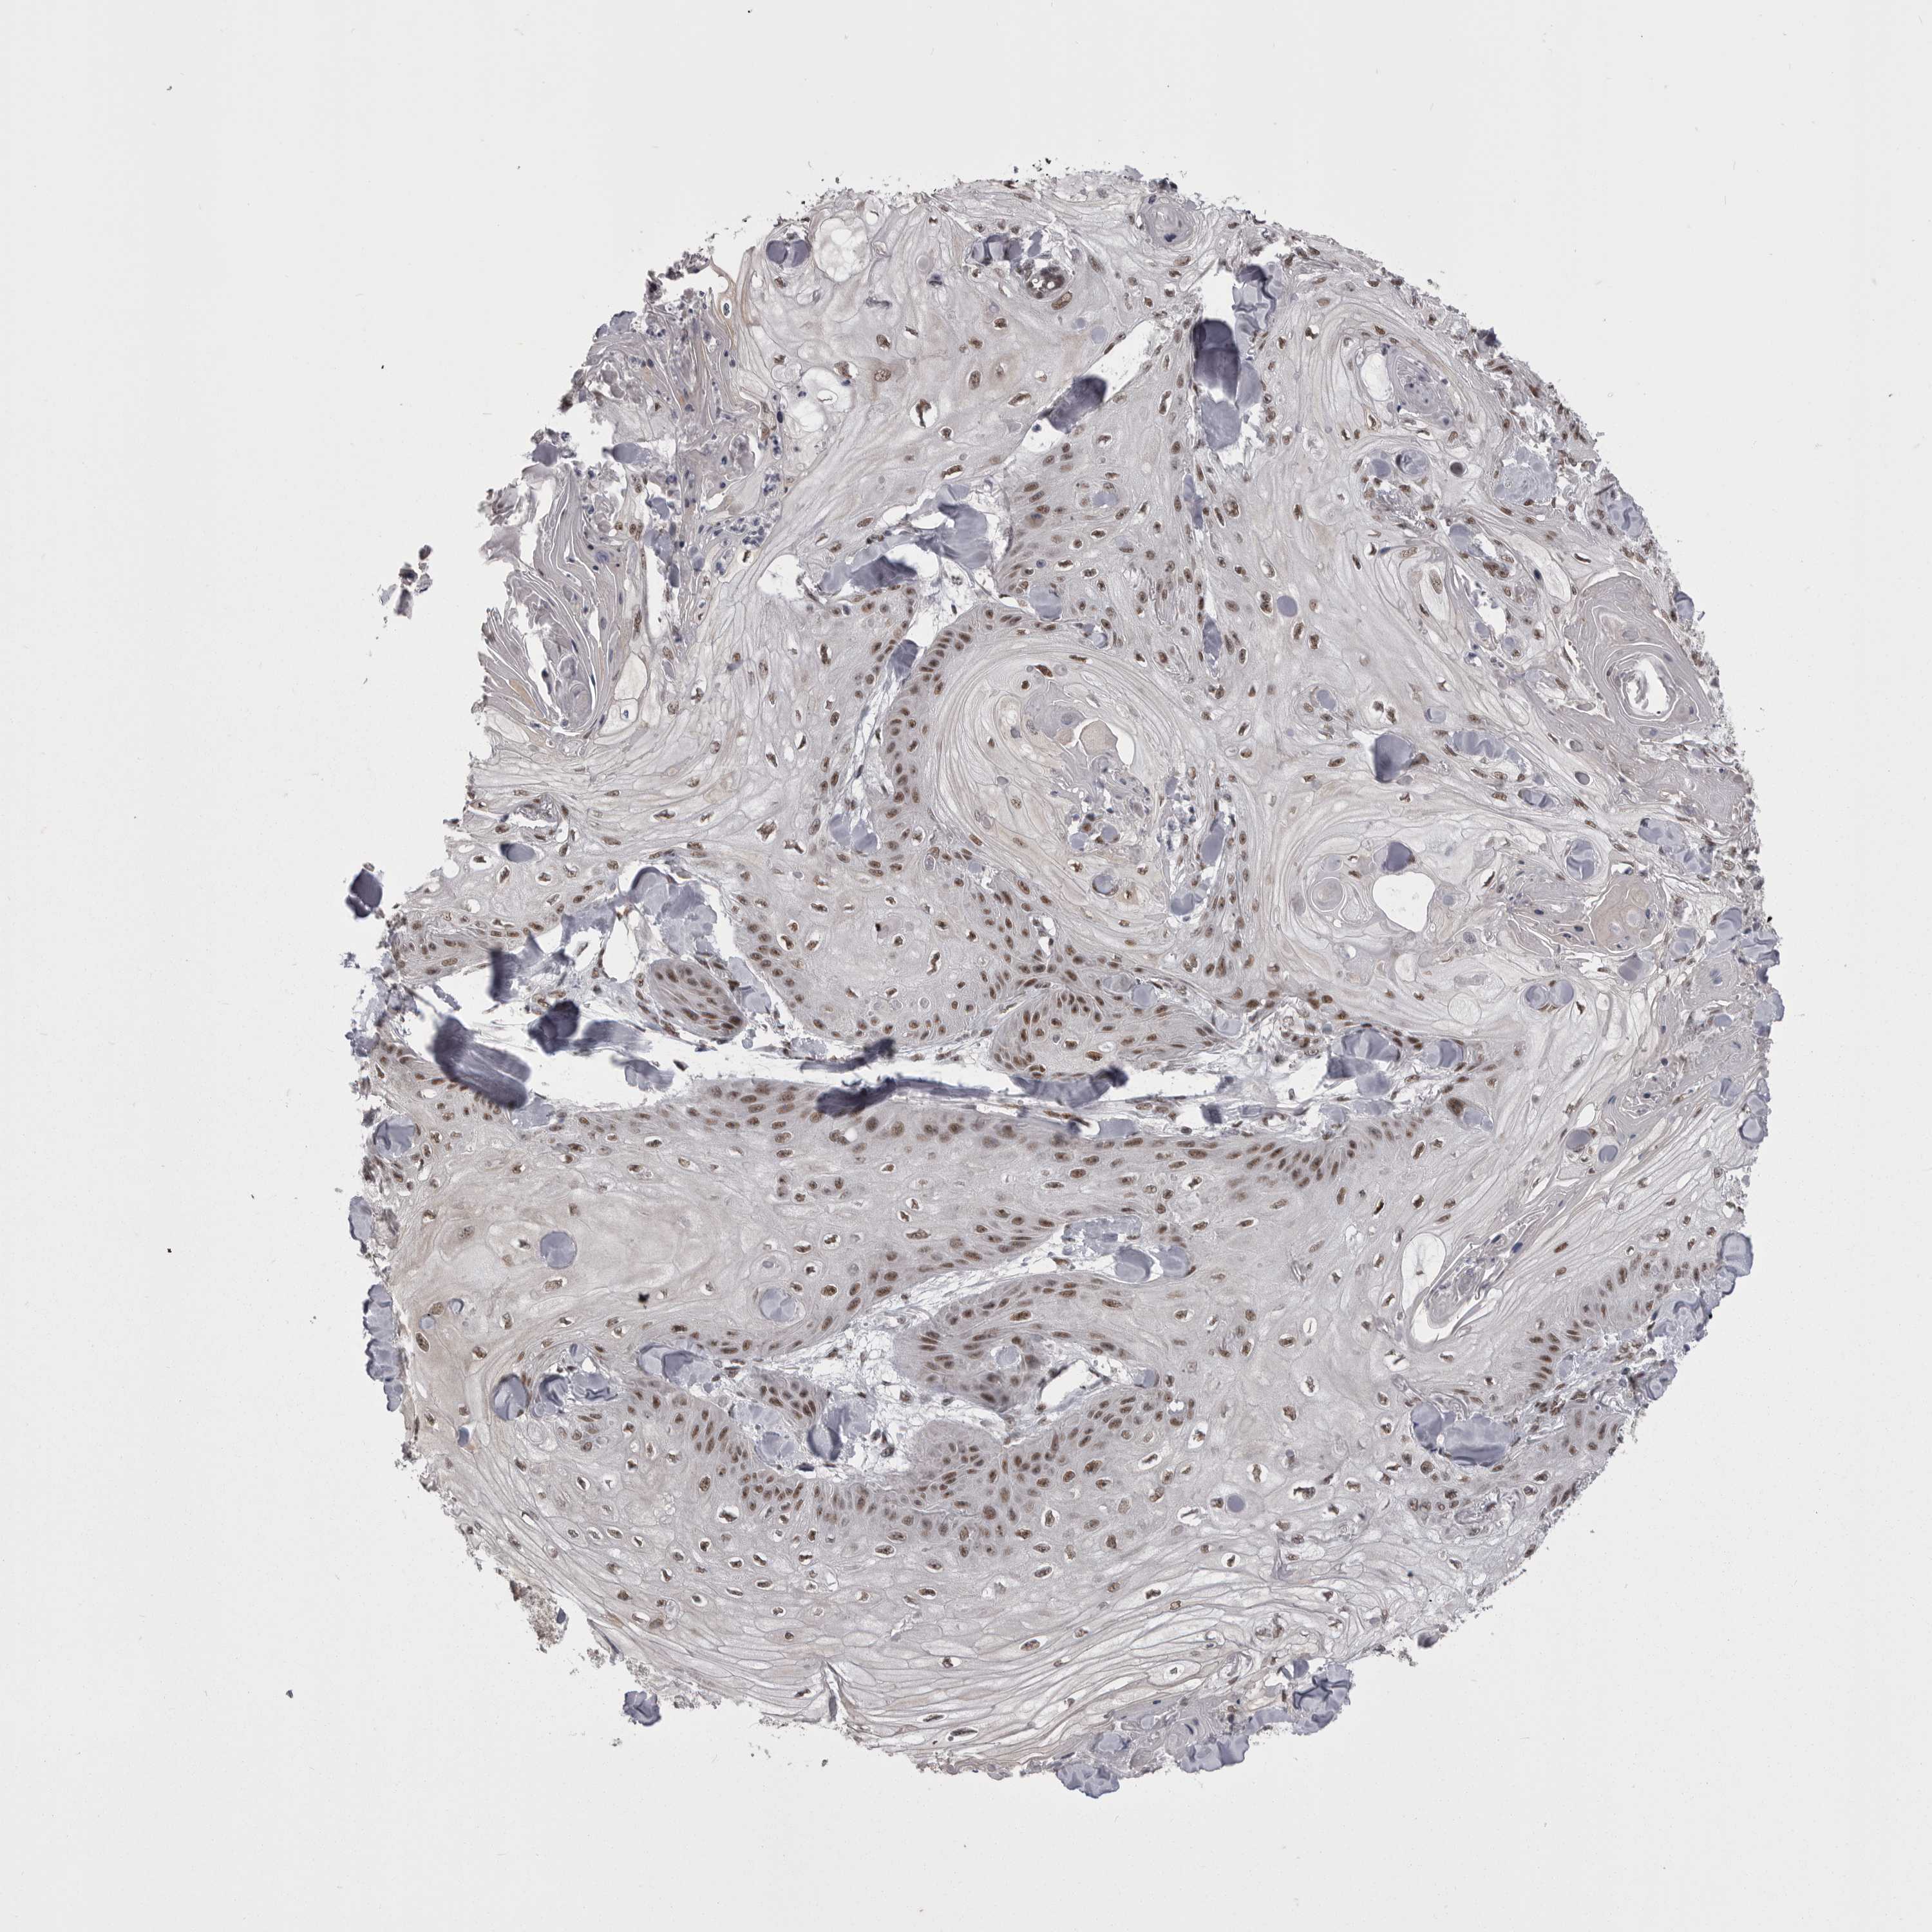

SKIN CANCER - Protein expressioni

A mouse-over function shows sample information and annotation data. Click on an image to view it in a full screen mode. Samples can be filtered based on level of antibody staining by selecting one or several of the following categories: high, medium, low and not detected. The assay and annotation is described here.

Antibody stainingi

Antibody staining in the annotated cell types in the current human tissue is reported as not detected, low, medium, or high, based on conventional immunohistochemistry profiling in selected tissues. This score is based on the combination of the staining intensity and fraction of stained cells.

Each image is clickable and will lead to virtual microscopy that enables deeper exploration of all samples and also displays staining intensity scores, fraction scores and subcellular localization as well as patient and tissue information for each sample.

Antibody HPA051587

Antibody CAB026384

Staining

High

Medium

Low

Not detected

Intensity

Strong

Moderate

Weak

Negative

Quantity

>75%

75%-25%

<25%

None

Location

Nuclear

Cytoplasmic/membranous

Cytoplasmic/membranous,nuclear

Squamous cell carcinoma, metastatic, NOS

Squamous cell carcinoma, NOS